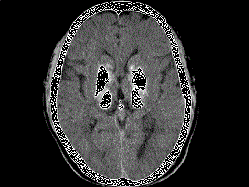

问题 男,49岁,反复发作性癫痫,双手震颤5年,伴头昏行走不稳,生化检查:血清钙降低,血清磷升高,请根据所提供图像,选择最可能的诊断 ( )

选项 A、肝豆状核变性 B、甲旁低 C、一氧化碳中毒性脑病 D、霉变甘蔗中毒 E、Fahr病

答案 B